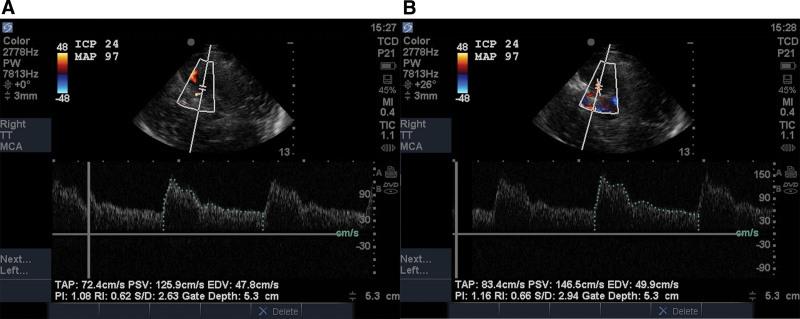

End-diastolic velocity (EDV), time-averaged peak velocity (TAPV), and pulsatility index (PI) were measured in the bilateral middle cerebral arteries with and without angle correction. Concomitant mean arterial pressure (MAP) and ICP were recorded. Estimated cerebral perfusion pressure (CPP) was calculated as estimated CPP (CPPe) = MAP × (EDV/TAPV) + 14, and estimated ICP (ICPe) = MAP-CPPe. Sixty patients were enrolled and 55 underwent TCCS. Receiver operating characteristic curve analysis of ICPe for detection of invasive ICP greater than 22 mm Hg revealed area under the curve (AUC) 0.51 (0.37-0.64) without angle correction and 0.73 (0.58-0.84) with angle correction. The optimal threshold without angle correction was ICPe greater than 18 mm Hg with sensitivity 71% (29-96%) and specificity 28% (16-43%). With angle correction, the optimal threshold was ICPe greater than 21 mm Hg with sensitivity 100% (54-100%) and specificity 30% (17-46%). The AUC for PI was 0.61 (0.47-0.74) without angle correction and 0.70 (0.55-0.92) with angle correction.

在双侧大脑中动脉测量舒张末期速度(EDV)、时间平均峰值速度(TAPV)和搏动指数(PI),测量时使用和不使用角度校正。同时记录平均动脉压(MAP)和ICP。计算估计脑灌注压(CPP)为估计CPP(CPPe)=MAP×(EDV/TAPV)+14,估计ICP(ICPe)=MAP - CPPe。纳入60例患者,55例接受了TCCS检查。对检测有创ICP大于22 mmHg时的ICPe进行受试者操作特征曲线分析,结果显示未进行角度校正时曲线下面积(AUC)为0.51(0.37 - 0.64),进行角度校正时为0.73(0.58 - 0.84)。未进行角度校正时的最佳阈值为ICPe大于18 mmHg,灵敏度为71%(29 - 96%),特异度为28%(16 - 43%)。进行角度校正时,最佳阈值为ICPe大于21 mmHg,灵敏度为100%(54 - 100%),特异度为3%(17 - 46%)。PI的AUC在未进行角度校正时为0.61(0.47 - 0.74),进行角度校正时为0.70(0.55 - 0.92)。